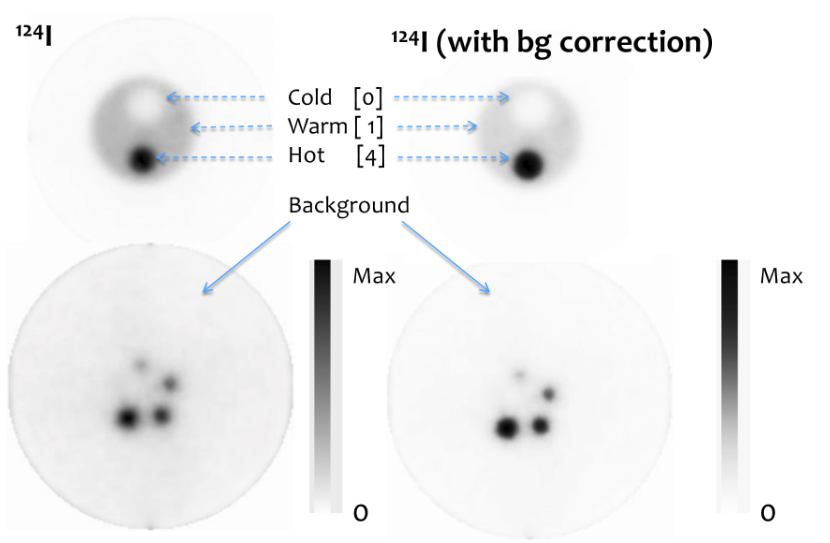

| ABSTRACT | Nonstandard PET radionuclides like 124 I, 76 Br, or 86 Y, emit prompt gamma rays together with the positrons which can be detected in coincidence with annihilation photons, creating spurious double coincidences. This causes a background in the PET images that reduces contrast and hampers quantitative accuracy. Existing correction methods are computationally intensive and since they depend on the size of the subject and on the accuracy of a number of complicated estimates, they may be valid for large source distributions only up to a certain size. To overcome these challenges, we have implemented a novel correction which is based on the measurement of positron+gamma triple coincidences. |